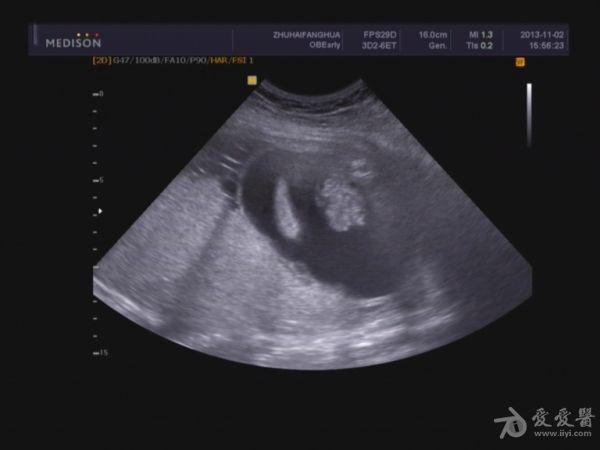

胎盘:附着于子宫后壁,厚度44mm,成熟度:0级,范围面积大,几乎覆着全后壁。

3.超大胎盘,羊水少。

因为羊水少,很多部位观察不清,四维图片基本没意义。期待几天后引产看结果。